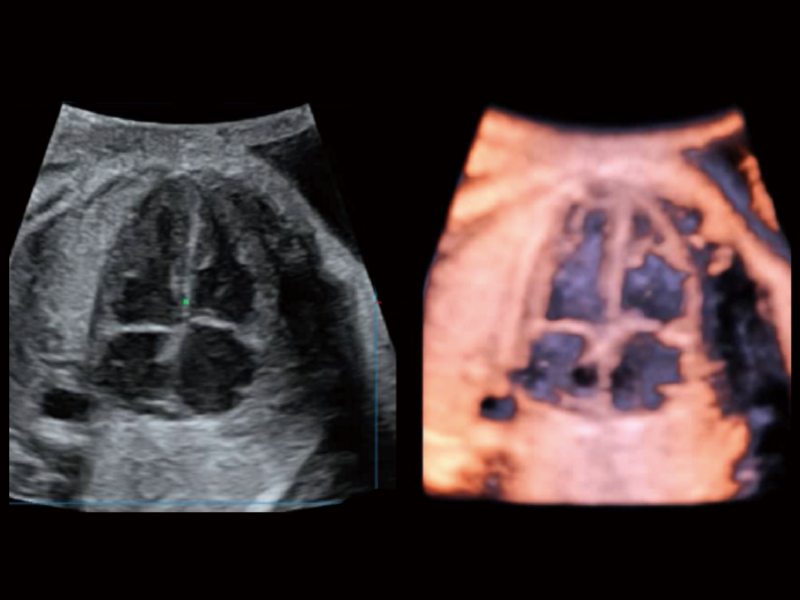

在传统血流的基础上优化扫查和算法策略,能够更好的抑制组织信息,提炼红细胞运动信息,得到更高帧频,高灵敏度和分辨率的血流信号,还原更真实的血流动力学。

通过光照模型,使二维血流显示出立体的效果,增加血流的敏感性、成束性,减少外溢。可以和其他不同的血流技术联合使用,融合不同技术的优势。轻松应对微小血管,增强血流的立体效果,提升视觉敏感性。

通过创新的Matrix E自适应滤波算法,能有效滤除软组织和噪声信号,最大限度保留超低速微细血流的信号;结合超长时间域算法,极大提升细微血流的敏感性和空间分辨率,更真实的反应组织、包块的血流灌注情况。